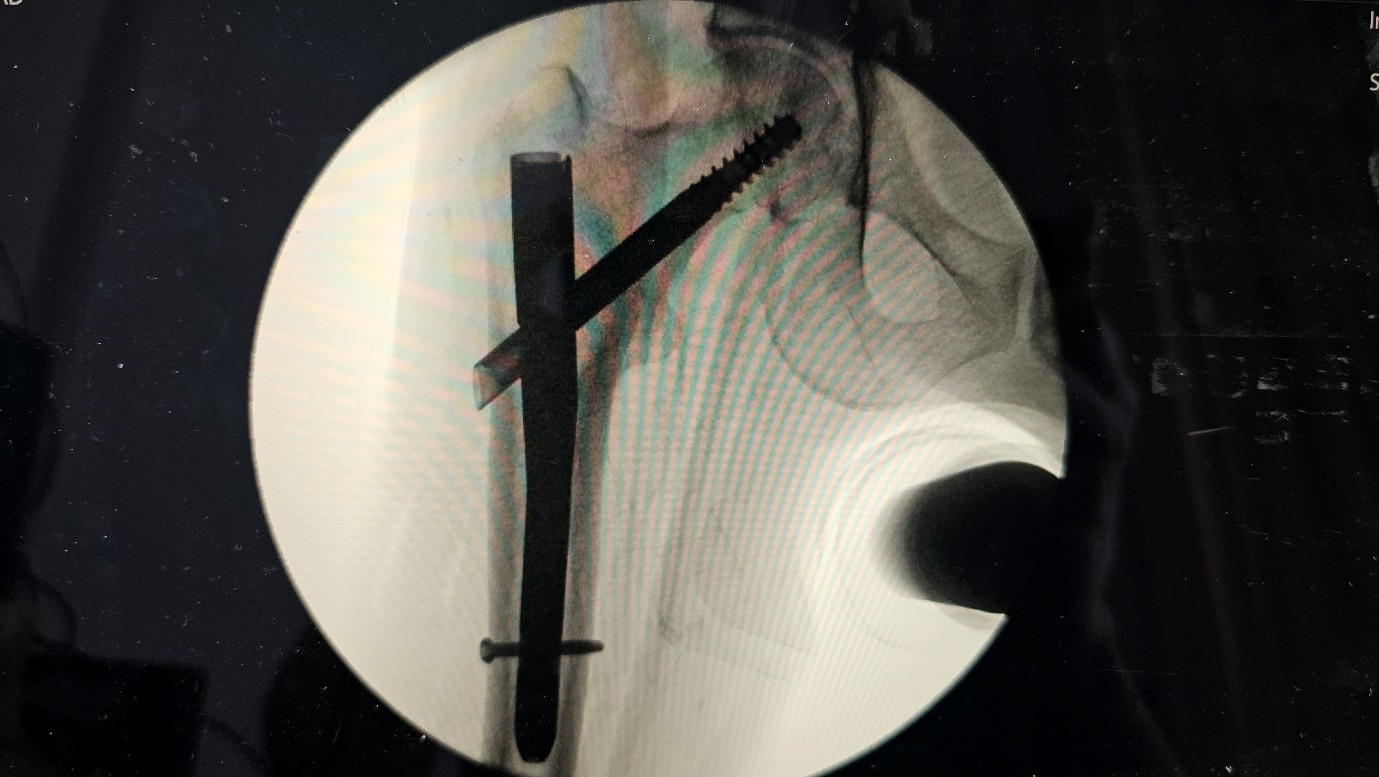

The patient underwent internal fixation using a Trochanteric Fixation Nail Advanced (TFNA). Intraoperatively, fracture reduction was suboptimal, with mild varus malalignment. The entry point for the nail was slightly lateral, and the cephalic screw was inserted in an inferior-anterior position. Intraoperative fluoroscopy showed acceptable placement, although the exact position of the screw could not be fully assessed.

Post first surgery :

Fig 3

Fig 4

Figure 3

Figure 4